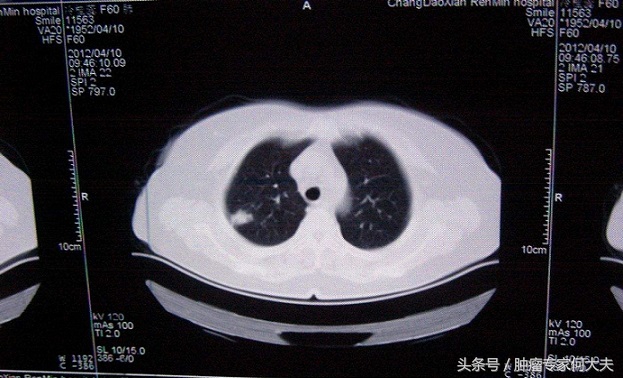

早期(I或II期)肺癌,究竟该如何治疗? 肺癌是人类第一大癌症,发病率和死亡率都极高,随着人们健康体检意识的加强,早期肺癌检出率越来越高。今天就有一个病人,男性,52岁,刚被确诊早期肺癌,咨询可否单纯中药治疗,被我否决了,那么被确诊早期肺癌,究竟该如何治疗呢?